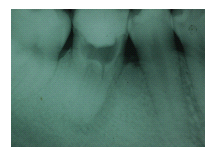

43歲女性病人,如圖1A所示。病人由其他醫師轉診來拔除左下顎嚴重蛀牙的第二大臼齒與阻生智齒,理論上如果拔除此第二大臼齒後,必須以人工植牙重建之,但是病人有經濟上的考量,因此與病人討論過後,決定將同時欲拔除的 阻生智齒移植入第二大臼齒齒槽,雖然病人年紀稍大,仍值得一試,圖1B 是術後一個月的X光片,由於病人年紀較大,智齒在植入缺牙區域時,已同時作根管治療,圖1C是術後四個月的X光片,根管內充填的是Vitapex(Ca(OH)2),圖1D是術後一年四個月後的X光片,智齒牙根尖的骨頭已經全部再生回來,而且牙根無黏連的情形,臨床上牙齒動搖度小於1,牙周組織健康,而其前面的第一大臼齒情況良好,咬合正常。

圖1C

圖1D